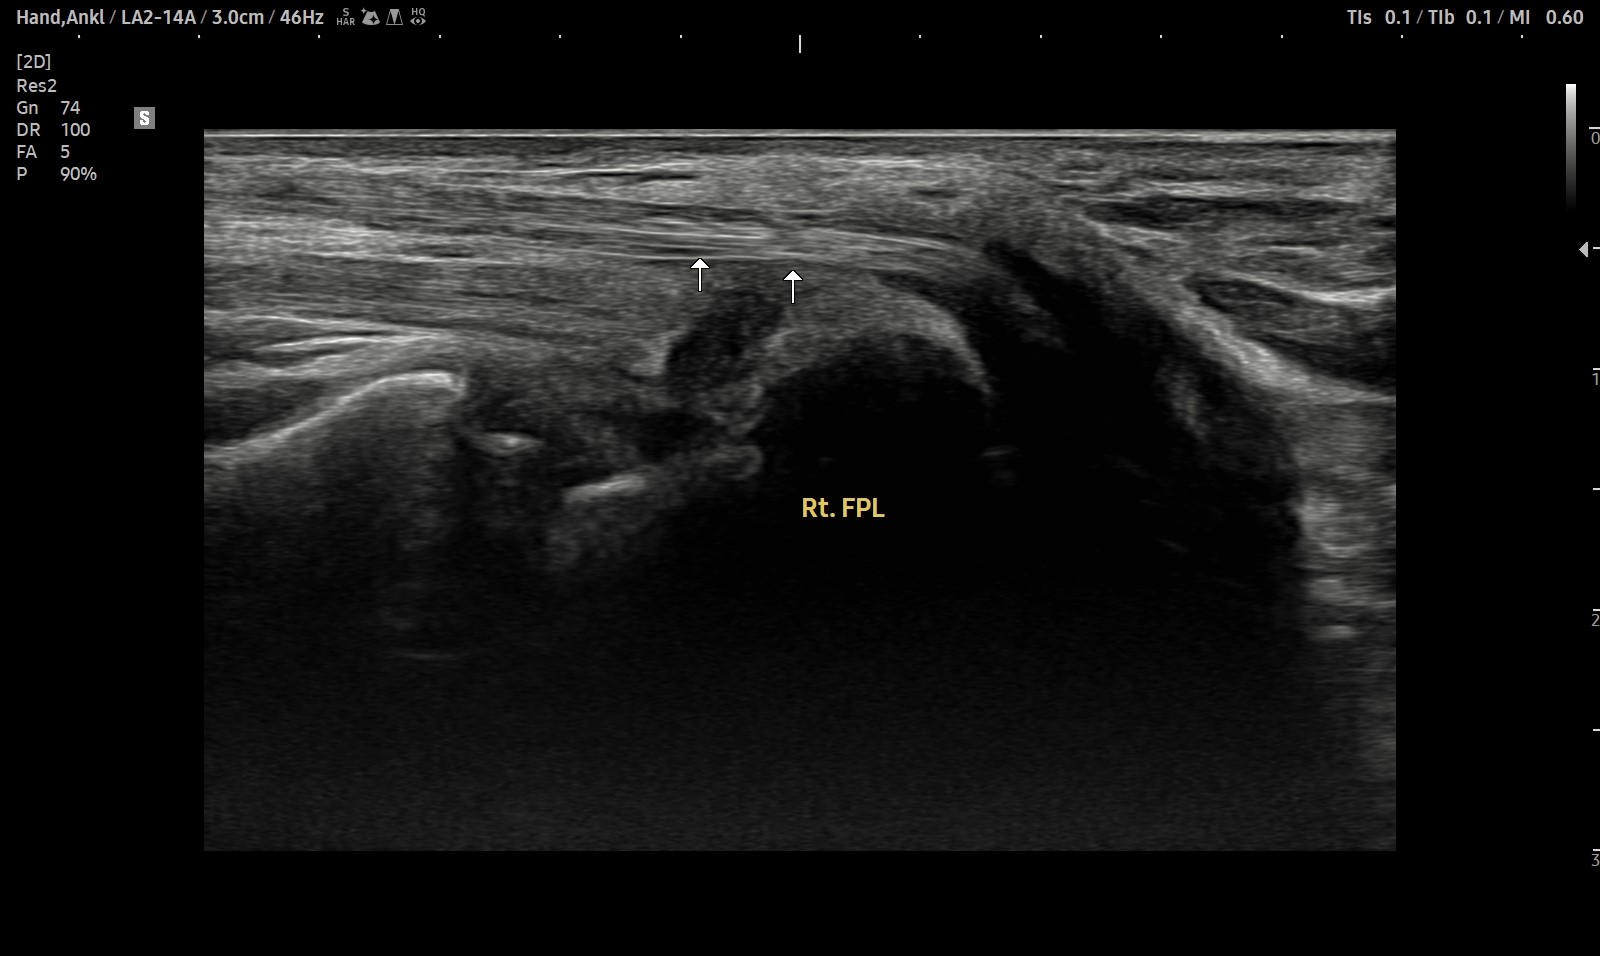

- 치료기간 : 25 . 5 . 7 ~ 25 . 8 .12

- 치료횟수 : 4cycle(20) 회

치료전

치료후